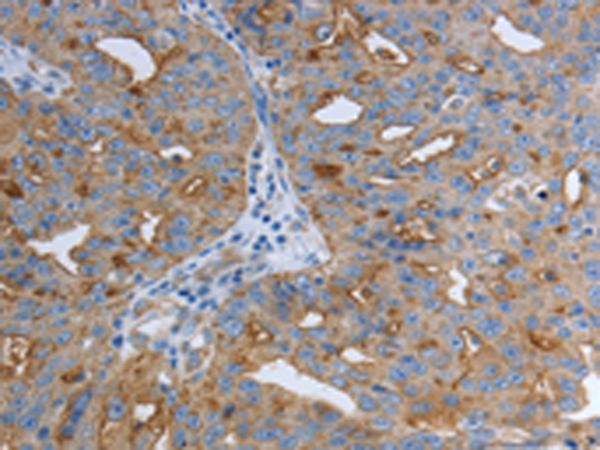

分类: 科研抗体货号: P11106别名:应用: WB,IHC反应种属: Human, Mouse, Rat